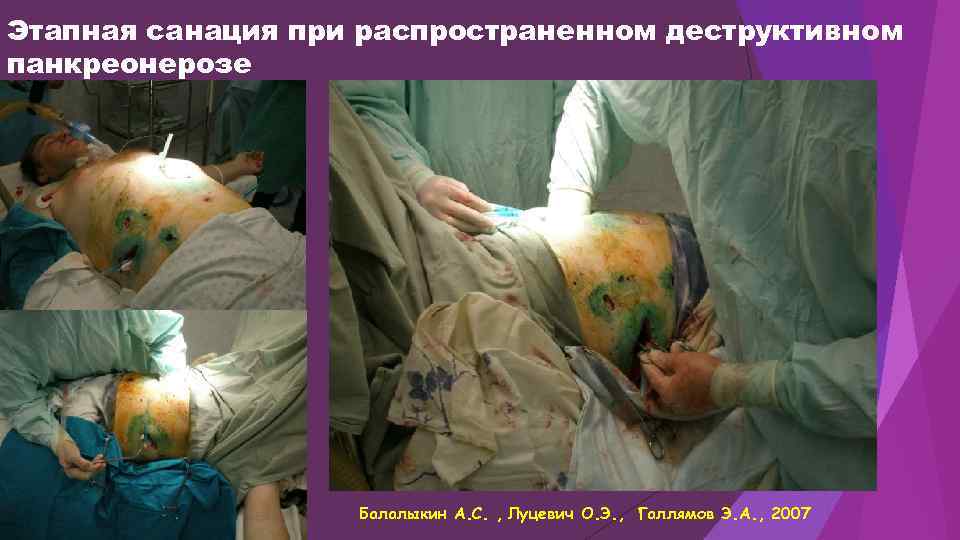

Этапная санация при распространенном деструктивном панкреонерозе Балалыкин А. С. , Луцевич О. Э. , Галлямов Э. А. , 2007

Этапная санация при распространенном деструктивном панкреонерозе Балалыкин А. С. , Луцевич О. Э. , Галлямов Э. А. , 2007

Этапная санация при распространенном деструктивном панкреонерозе Балалыкин А. С. , Луцевич О. Э. , Галлямов Э. А. , 2007

Этапная санация при распространенном деструктивном панкреонерозе Балалыкин А. С. , Луцевич О. Э. , Галлямов Э. А. , 2007